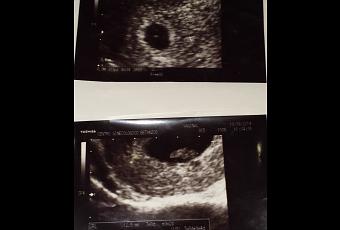

Me he hecho dos ecografías en forma particular porque en la seguridad social recién me dan la primera para la semana 11. En la primera, que estaba de 5 semanas, mi garbancito sólo medía 1 mm y estaba muy bien ubicado, pero aún no se le distinguía el corazón. Volvimos en la semana 7 y ya medía más de 1 cm y lo más bonito e importante es que pude ver claramente como latía su pequeño pero hermoso corazón…(Aquí dejo las ecos).